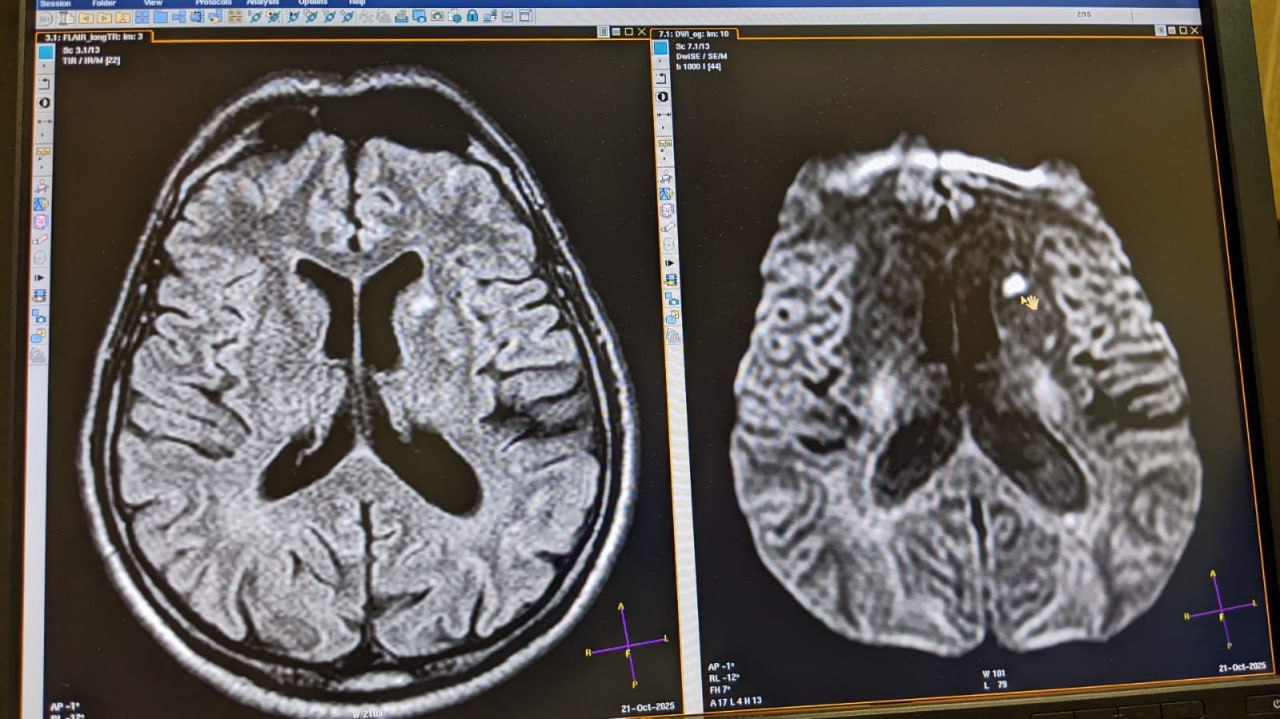

По результатам МРТ головного мозга выявлены острые ишемические очаги в лобных долях головного мозга. То есть, нарушено кровообращение мозга!